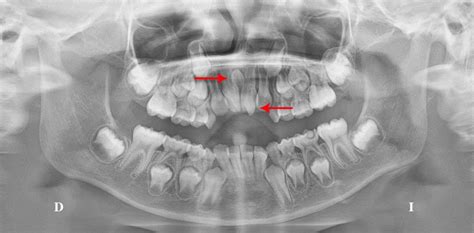

Un diente supernumerario es una pieza dentaria adicional a la formula normal (20 dientes en la dentición temporal y 32 en la permanentes). Los dientes supernumerarios son dientes extra de la dentadura habitual, pero no tienen la forma de diente tal y como la conocemos. Estos dientes pueden presentarse en las diferentes etapas del desarrollo humano, tanto en la dentición temporal como en la mixta y permanente; constituyen uno de los factores que se asocian a la etiología de las maloclusiones y ocasionan alteraciones en la línea media, retención de piezas dentarias, apiñamientos, resorción radicular, diastemas y malformación de otros dientes. Se encuentran en cualquier región del arco y sólo se pueden visualizar radiográficamente.

Identificar un diente supernumerario puede ser muy complicado. La mayoría de estos dientes no llegan a asomar en la encía o el paladar, por lo que se recomienda realizar una radiografía de vez en cuando para identificar este problema de forma prematura. Su diagnóstico se realiza mediante un estudio radiológico (radiografía panorámica). El diagnóstico temprano de los dientes supernumerarios es importante para evitar que se presenten complicaciones. Éste puede realizarse a través de la exploración clínica y radiográfica y su tratamiento dependerá de la posición y clase de supernumerario, así como el efecto sobre el diente temporal o permanente.